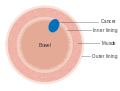

The T stages of bowel cancer. Dukes stage A bowel cancer; the cancer is only in the inner lining of the bowel.

Dukes stage A bowel cancer; the cancer is only in the inner lining of the bowel. Dukes stage B bowel cancer; the cancer has invaded the muscle.